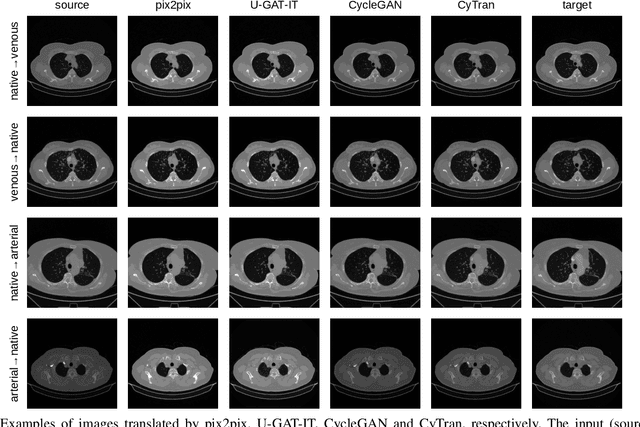

Abstract:We propose a novel approach to translate unpaired contrast computed tomography (CT) scans to non-contrast CT scans and the other way around. Solving this task has two important applications: (i) to automatically generate contrast CT scans for patients for whom injecting contrast substance is not an option, and (ii) to enhance alignment between contrast and non-contrast CT by reducing the differences induced by the contrast substance before registration. Our approach is based on cycle-consistent generative adversarial convolutional transformers, for short, CyTran. Our neural model can be trained on unpaired images, due to the integration of a cycle-consistency loss. To deal with high-resolution images, we design a hybrid architecture based on convolutional and multi-head attention layers. In addition, we introduce a novel data set, Coltea-Lung-CT-100W, containing 3D triphasic lung CT scans (with a total of 37,290 images) collected from 100 female patients. Each scan contains three phases (non-contrast, early portal venous, and late arterial), allowing us to perform experiments to compare our novel approach with state-of-the-art methods for image style transfer. Our empirical results show that CyTran outperforms all competing methods. Moreover, we show that CyTran can be employed as a preliminary step to improve a state-of-the-art medical image alignment method. We release our novel model and data set as open source at: https://github.com/ristea/cycle-transformer.